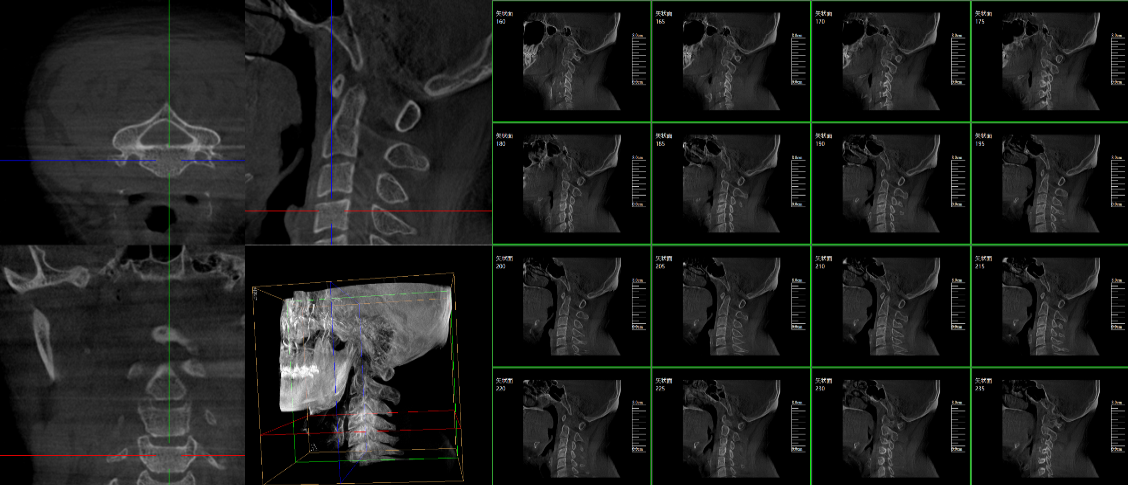

三維C臂,作為“術中CT”,能在術中快速地生成橫斷面、矢狀面、冠狀面和可旋轉的立體圖像,給術者提供360°無死角的觀察角度,全方位準確判斷骨組織和植入物的情況,為手術的實施提供保障,極大提高手術成功率,減少并發癥概率。主要適用于骨科、脊柱外科、矯形外科、創傷骨科及手術室等。

普愛醫療三維C形臂具備術中實時三維成像,術中三維成像和橫斷面圖像提供多角度的手術診斷信息,輔助醫生進行術中評估判斷,諸如骨折復位情況和內植入螺釘的尺寸和位置,輔助手術更好地完成;三維成像視野大,提供更大的術中三維成像視野,采集更多圖像信息,可一次拍全全段頸椎、全段腰椎、七節胸椎、雙側骶骼關節、股骨頭及單側盆骨等。如果您想了解更多普愛三維C形臂優點及技術參數,歡迎咨詢我們。